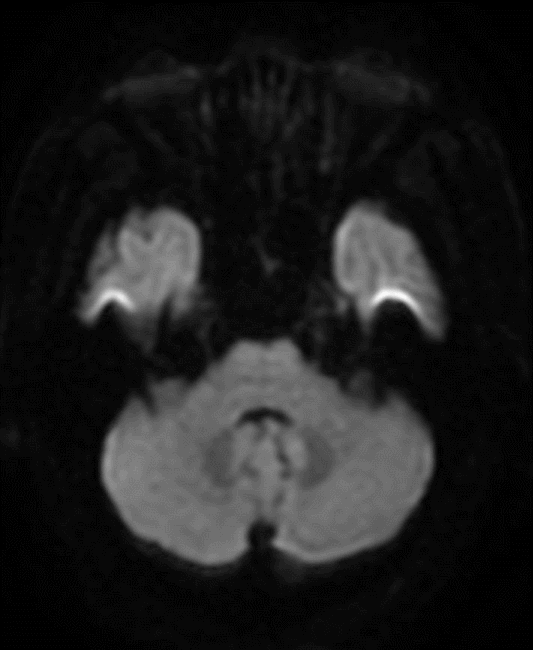

🔆  行头MRI+MRA示:右侧丘脑亚急性脑梗塞;轻度脑萎缩;部分空泡蝶鞍;脑动脉硬化并多组脑动脉轻度狭窄;右侧颈内动脉虹吸段外动脉瘤待排。

术前影像

MRI+MRA

脑血管造影提示右侧颈内动脉颅内段多发动脉瘤(反主动脉弓)

脑血管造影提示右侧颈内动脉颅内段多发动脉瘤